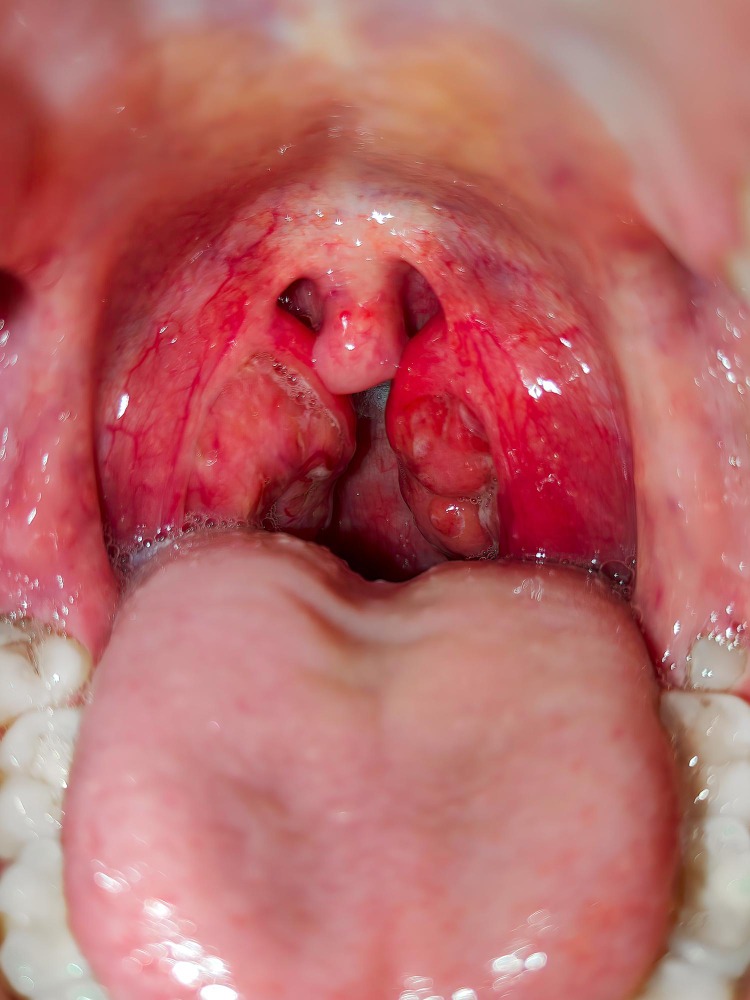

Šarlachová angína je bakteriálna infekcia hrdla a mandlí, ktorá spôsobuje silný zápal, bolesť a škrabanie hrdla. Je spôsobená tou istou baktériou, ktorá spôsobuje streptokokovú angínu — Streptococcus pyogenes, tiež nazývaný streptokok skupiny A.

Pri šarlachovej infekcii však baktéria uvoľňuje toxín (erytrogénny pyrogénny exotoxín), ktorý okrem bolesti hrdla vyvoláva aj výraznú kožnú vyrážku a červený (malinový) jazyk. Vzniká tak ochorenie nazývané šarlach. Najčastejšie sa vyskytuje u detí vo veku 5 až 15 rokov.

„Šarlach je syndróm charakterizovaný blednúcou, začervenanou vyrážkou, často popisovanou ako „piesková“, jahodovým jazykom a exsudatívnou faryngitídou. Tieto príznaky silne naznačujú šarlach ako hlavný diagnostický predpoklad.“ (Pardo, S., & Perera, T. B., 2025)